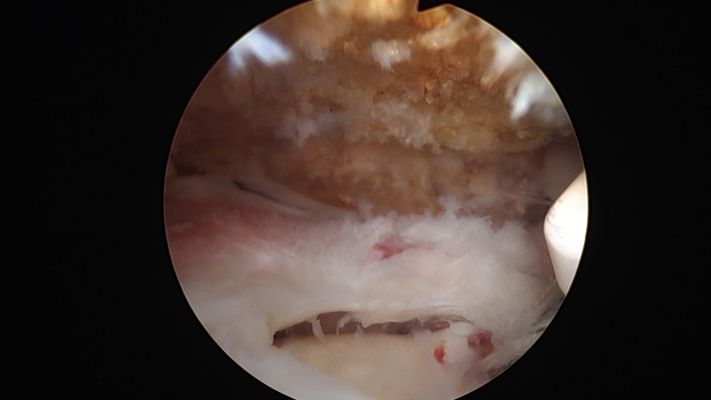

La artroscopia se realiza mediante pequeñas incisiones de aproximadamente 0,5 a 1 cm, con la ayuda de una cámara podemos ver el interior del hombro e identificar la rotura del tendón y se repara utilizando unos tornillos o anclajes cargados con hilos muy fuertes para fijar el tendón en el lugar correcto.

Resultado después de reparación por artroscopia.

Antes y después (reparación de rotura completa del supraespinoso)